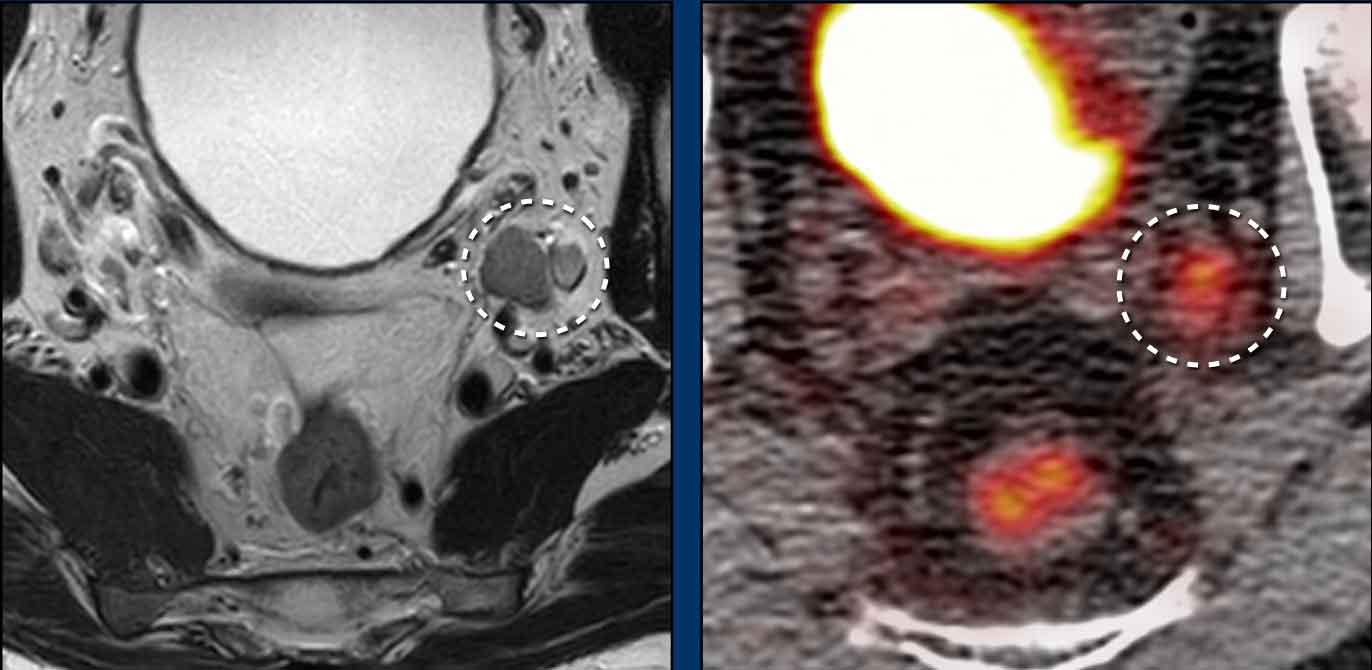

Các hình ảnh này của một bệnh nhân ung thư hậu môn.

Hình ảnh

MRI cho thấy một hạch bạch huyết to rõ rệt (đường kính trục ngắn 1,5 cm) liền kề mạch chậu trong, được phân giai đoạn là N+ trên MRI.

FDG-PET CT cho thấy tăng hấp thu FDG bệnh lý tại hạch, xác nhận đây là hạch N+.

Trong trường hợp này có hai hạch bạch huyết nhỏ trong mạc treo trực tràng được đánh giá là không rõ ràng trên MRI.

FDG-PET cho thấy tăng hấp thu FDG rõ rệt tại các hạch nhỏ này, thể hiện lợi ích bổ sung của PET so với MRI trong phân giai đoạn hạch ung thư hậu môn.

Bệnh nhân cuối cùng được phân giai đoạn là T2 N1a.